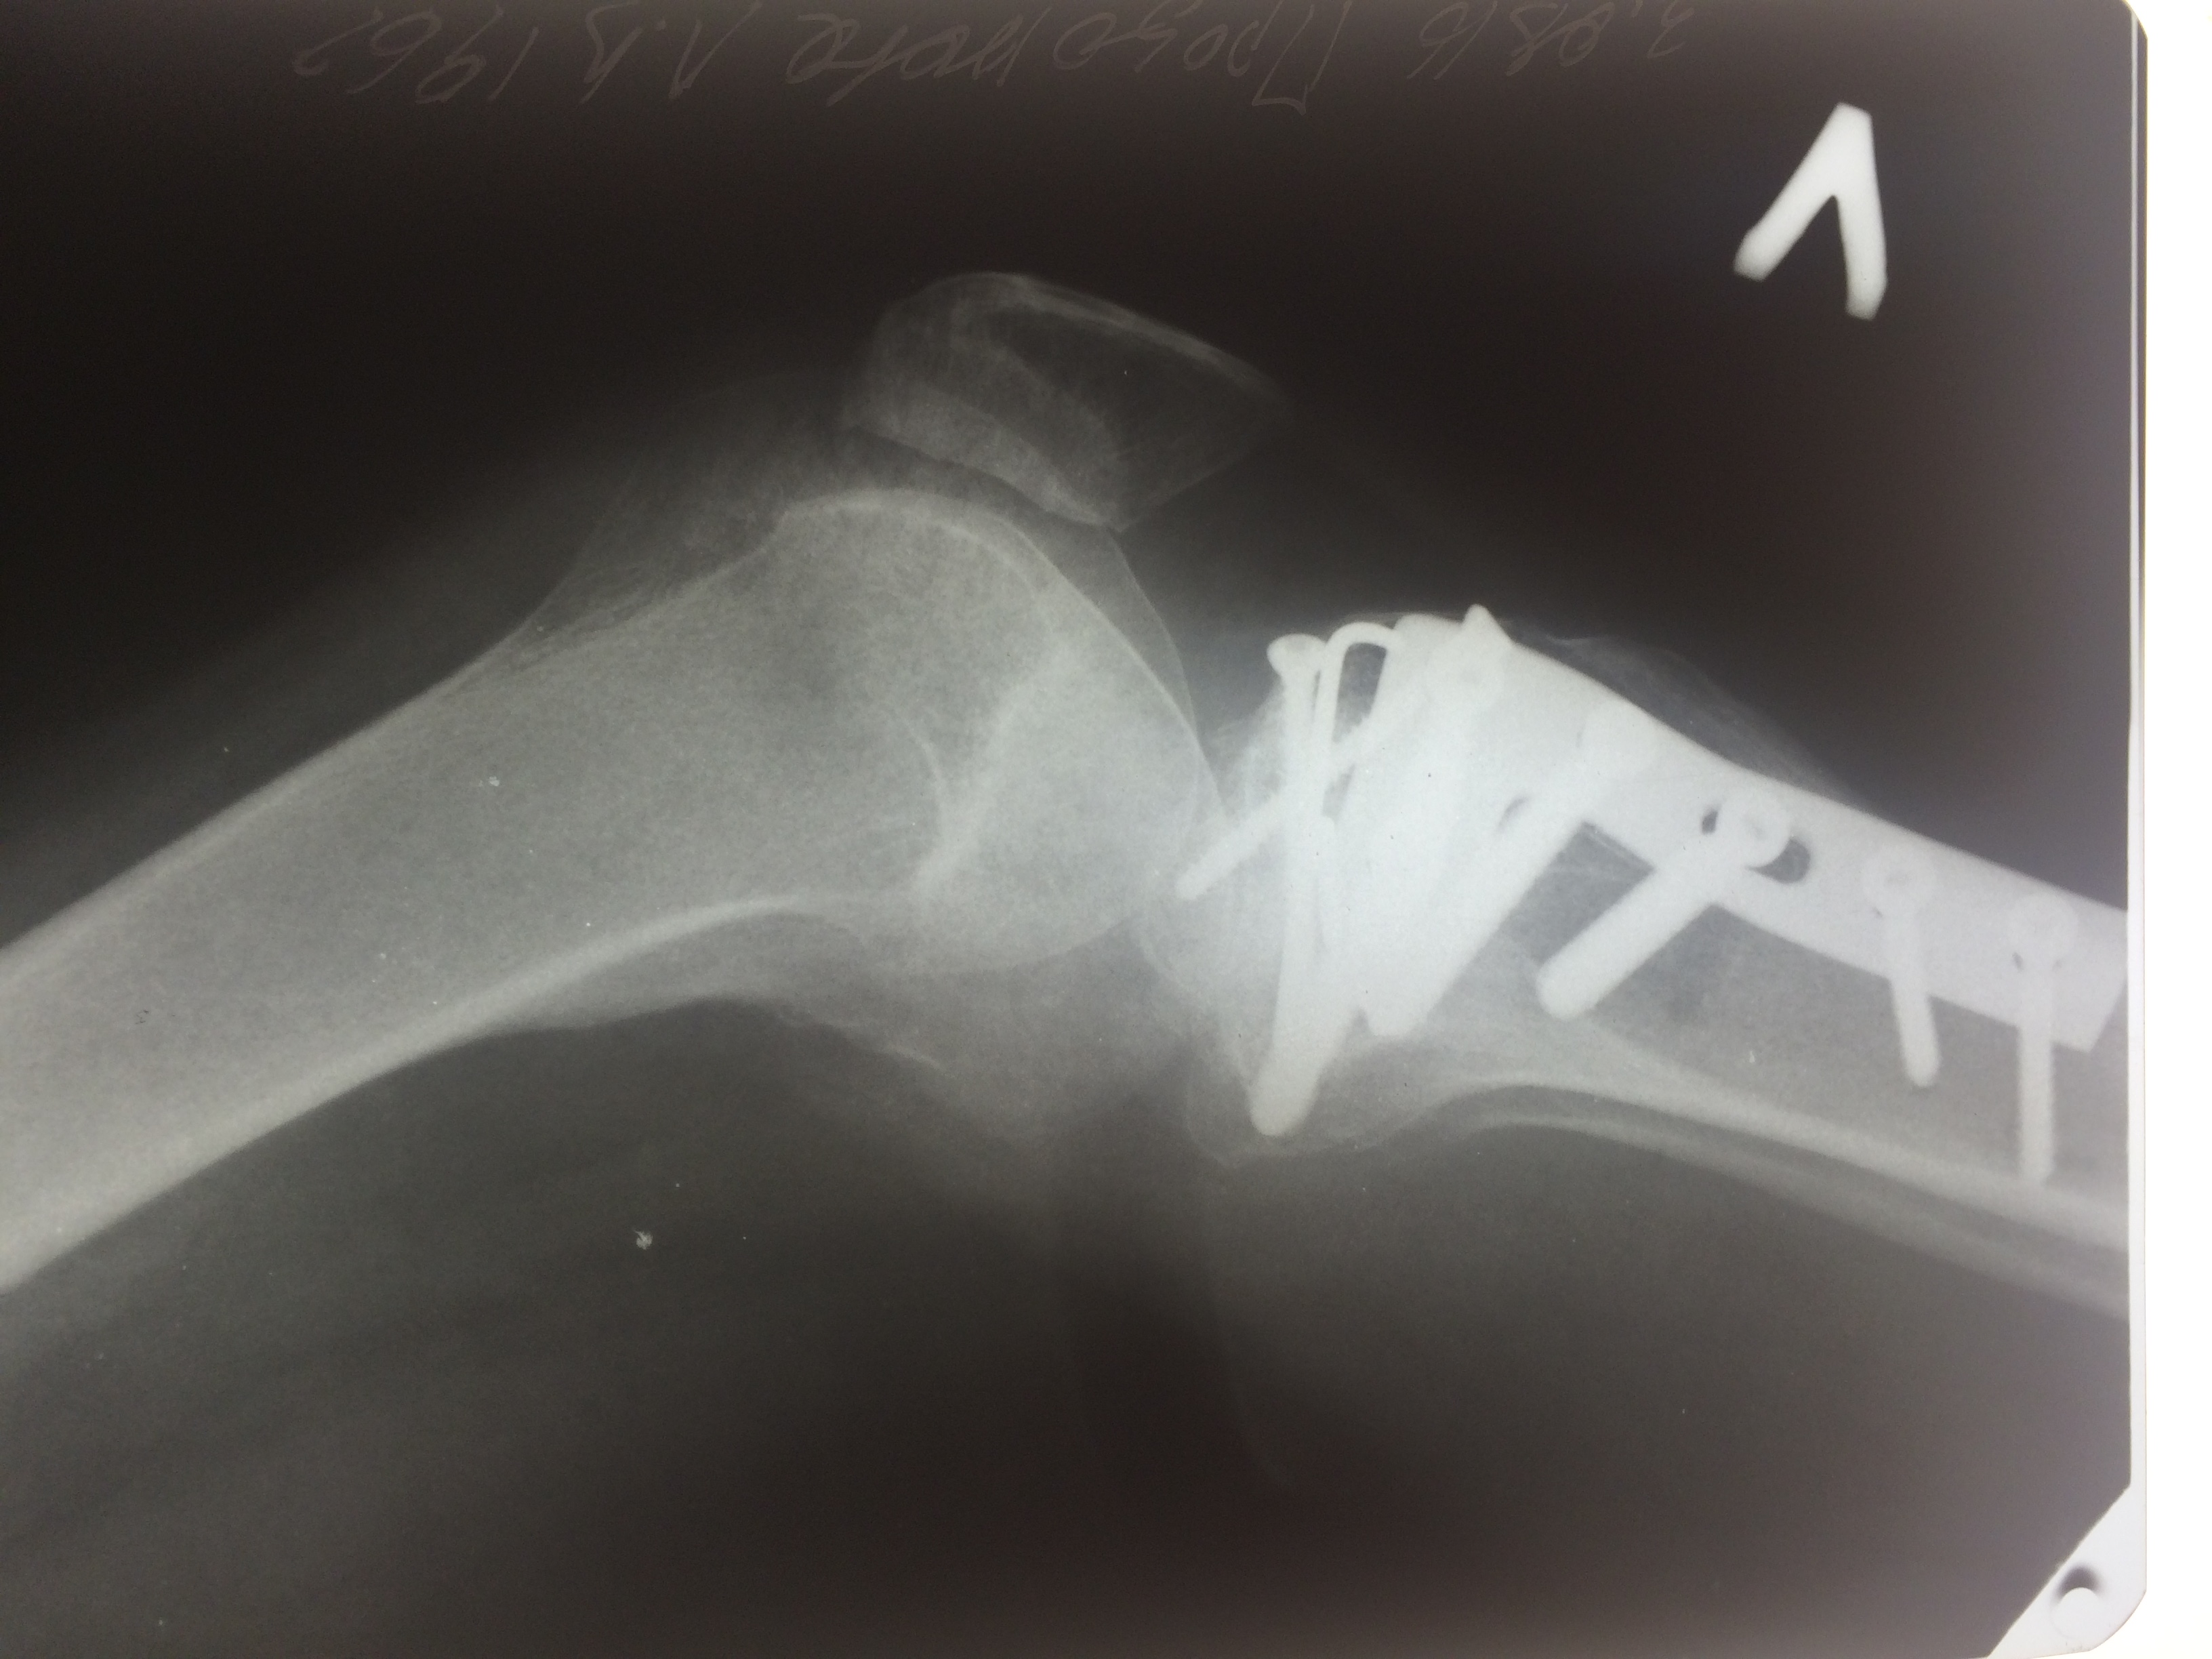

Операция - открытая репозиция, остеосинтез большеберцовой кости опорной пластиной с костной ксенопластикой маетриалом "Остеоматрикс". На контрольных снимках в три и шесть месяцев имеется консолидация перелома, миграции фиксатора нет, имеется остеоинтеграция ксенопластического материала. Функция коленного сустава полная.

Отдаленные результаты через 3 (три) месяца